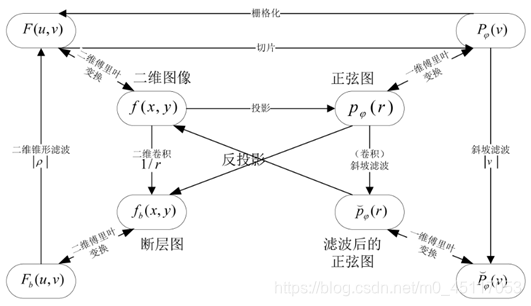

二维图像的投影,就是射线以一定角度穿透物体的衰减值。图像重建的过程包含反投影,就是由这些不同角度(0~180°)下的投影值恢复原始图像。恢复的方法有很多种。下图概括了各种空间的转换关系。